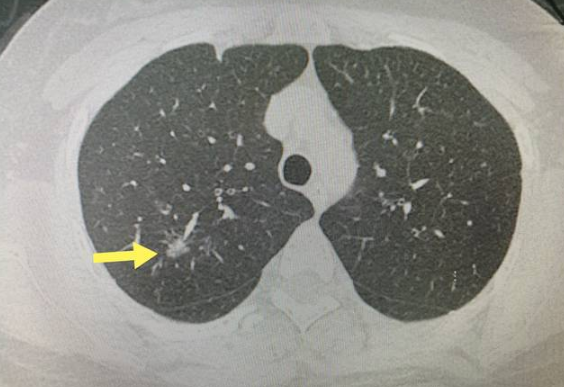

影像科——肺部磨玻璃结节一定要手术吗

肺部磨玻璃结节一定要手术吗 随着低剂量CT的普及,肺部疾病的筛查越来越被重视。如果您的报告上,写着“肺部磨玻璃结节”的字样,您会不会瞬间紧张起来?磨玻璃…